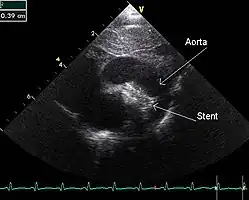

PDA is usually diagnosed using noninvasive techniques. Echocardiography (in which sound waves are used to capture the motion of the heart) and associated Doppler studies are the primary methods of detecting PDA. Electrocardiography (ECG), in which electrodes are used to record the electrical activity of the heart, is not particularly helpful as no specific rhythms or ECG patterns can be used to detect PDA.[8]

An echocardiogram of a stented persisting ductus arteriosus: One can see the aortic arch and the stent leaving. The pulmonary artery is not seen. -